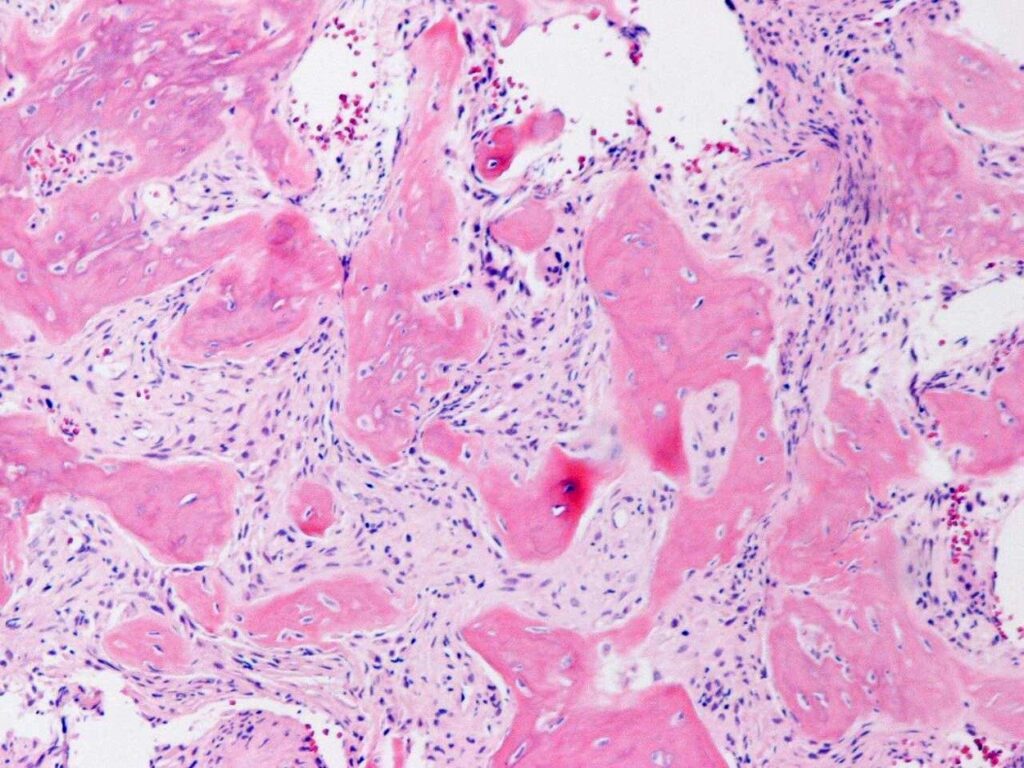

PATHOLOGY

Low Grade Intraosseous Osteosarcoma is a low-grade malignancy, similar to parosteal osteosarcoma.

Microscopic

• Display bundles of spindle cell proliferations with variable osteoid production, low cellularity, low mitotic rate, and minimal pleomorphism (Fig. 9 & 10).

• The presence of infiltrative margins and the absence of marked cellular atypia helps to differentiate low grade intraosseous osteosarcoma from benign entities.

Fig. 9 & 10: Microscopic Pathology. Low and high power views with irregular woven bone trabeculae in a moderately cellular fibrous tissue. Atypical cells displaying hyperchromatic nuclei are closely associated with the irregular woven bone trabeculae.